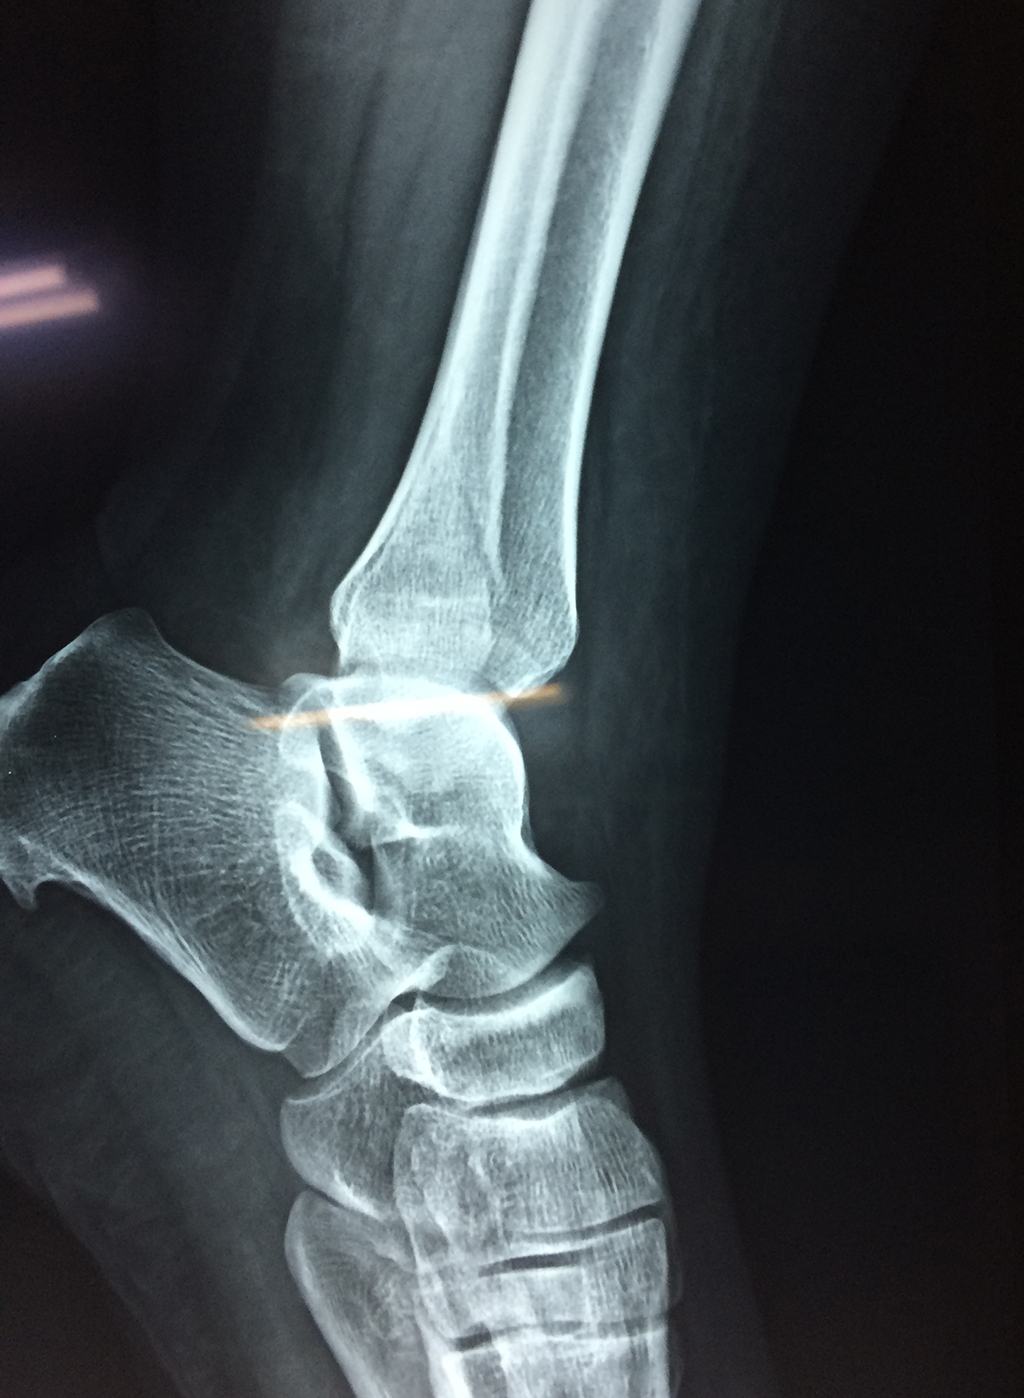

Una fractura de tobillo es la rotura de uno o más de los huesos del tobillo. Estas fracturas pueden ser:

- Los extremos de los huesos están desalineados entre sí (desplazados).

- La fractura se extiende hasta la articulación del tobillo (fractura intra-articular).

Cuando se necesita cirugía, es probable que esta implique el uso de clavijas de metal, tornillos o placas para sostener los huesos en su lugar mientras la fractura se consolida. Los elementos de soporte pueden ser temporales o permanentes.